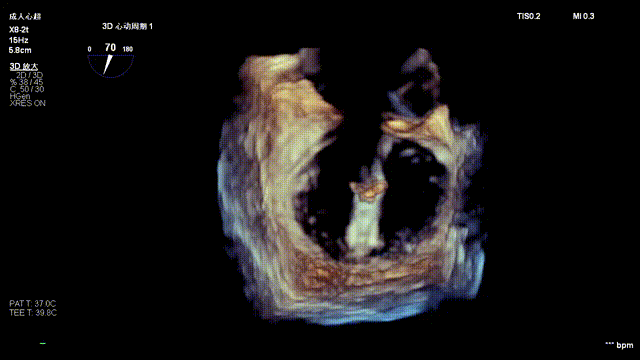

The operation was performed in a hybrid operating room and completed under the guidance of real-time three-dimensional transesophageal echocardiography (3D TEE) and X-ray fluoroscopy throughout the entire process.

3D color Doppler

Mitral valve Zone 2

Color Doppler of Mitral valve Zone 2